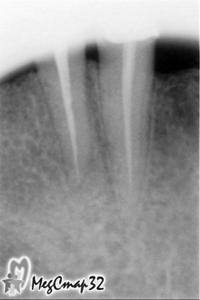

Через три недели со времени первого посещения в канал и за его верхушку,

был введен препарат для восстановления костной ткани около корня зуба (сн.№4).

Действие препарата проверялось контрольными снимками (сн.№5 сн.№6)

с интервалами 5 и 7 дней и оценивалось улучшение состояние зуба.